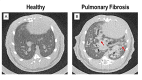

Acute respiratory distress syndrome (ARDS), chronic obstructive pulmonary disease (COPD), and pulmonary fibrosis are major respiratory conditions associated with significant morbidity and, in some cases, high mortality. A variety of animals models have been established to study these disorders, primarily focusing on histologic alterations, cellular signalling pathways, inflammatory responses, lung perfusion, gas-exchange abnormalities, and response to emerging therapies. Imaging techniques play a crucial role in these investigations, enabling in vivo assessment of lung structure and function. The most widely used imaging modalities include computed tomography (CT), positron emission tomography (PET), and electrical impedance tomography (EIT). While CT and, to a variable extent, PET involve ionizing radiation, EIT is a radiation-free technique. Despite anatomical differences between species, many imaging and physiological findings observed in animal models are consistent with those seen in critically ill patients, enhancing their translational relevance. This narrative review provides a comprehensive overview of the applicability of these imaging techniques in animal models and explores their relevance to human pathophysiology and clinical management.